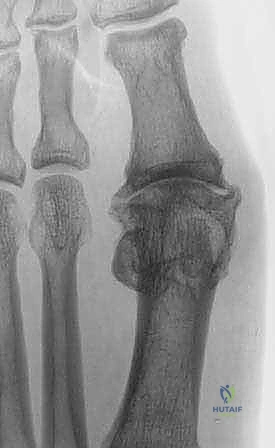

1. خشونة إبهام القدم المتقدمة (Hallux Rigidus)

يُعد هذا السبب الأكثر شيوعاً. وهي حالة من الفصال العظمي (Osteoarthritis) تصيب مفصل MTP الأول. مع مرور الوقت، يتآكل الغضروف الواقي، مما يؤدي إلى احتكاك العظم بالعظم. ينتج عن ذلك ألم شديد، وتيبس كامل في المفصل، وتكوين نتوءات عظمية (منقار عظمي) في الجزء العلوي من المفصل تمنع الإصبع من الانثناء للأعلى أثناء المشي.

في حالات الخشونة المتقدمة، يتآكل الغضروف الأملس تماماً، وتبرز زوائد عظمية (Osteophytes) تعيق حركة هذه الأوتار والأربطة، مما يسبب ألماً مبرحاً. جراحة الدمج تتدخل هنا لإزالة هذا الاحتكاك العظمي المدمر.